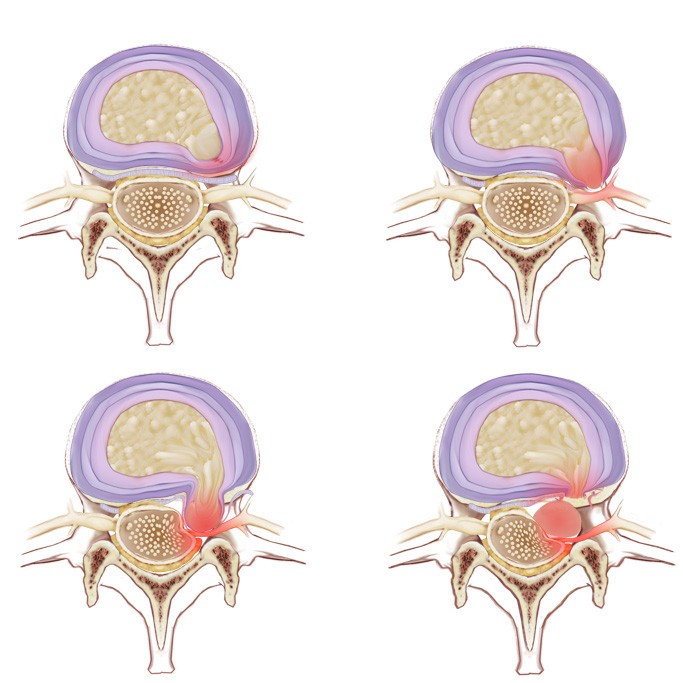

КТ-протрузии дисков: Визуализация и классификация